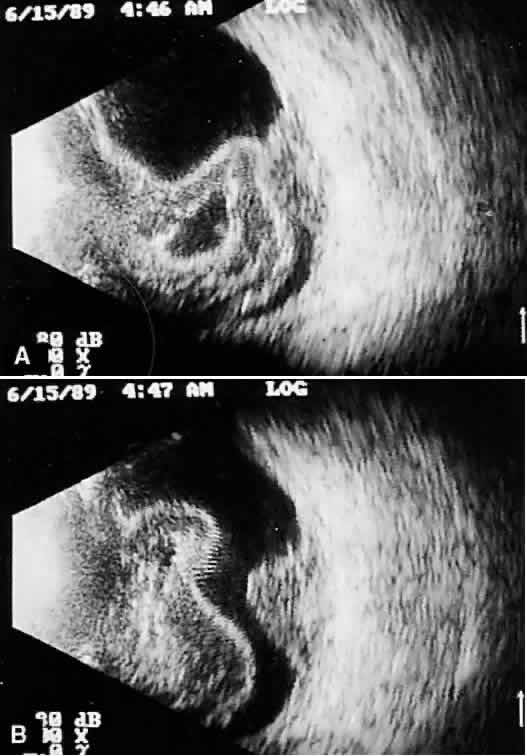

Real time refers to the display of motion or movement during B-scan imaging. This capability is one of the greatest advantages of B-scan. Differences in mobility of a variety of movable intraocular abnormalities can be easily detected. For example, the rapid movement of vitreous hemorrhage is usually easy to appreciate and differentiate from the slower, undulating movements of a recent, rhegmatogenous retinal detachment. On occasion, movement of intraocular structures can be used for detecting abnormalities that lie immediately behind vitreous opacification and may be seen only when the vitreous opacities are moved away from the ocular wall, set in motion by command voluntary movements of the patient's globe (Fig. 5). Gray scale refers to the variable gray tone of display screen echoes. Strong returning signals (echoes) appear white, whereas weaker reflections are seen as gray, the shade depending on echo strength. Examples of strong reflectors of sound include retinal tissue, sclera, and calcifications of any type (Fig. 6). Weaker echoes from clotted or clumped cells within the vitreous are usually easy to differentiate from the stronger reflectors of sound (Fig. 7). Grading of echo strength may be performed only when the examining ultrasound beam is perpendicular to the object of interest, ensuring the strongest possible reflections. However, in the world of ultrasound interpretation, there are many exception to the rules. Tissues that are usually mild reflectors of sound, such as hemorrhage, can at times appear quite strong, especially in complex or multiple pattern disorders, as frequently occur in severe ocular trauma. These apparent inconsistencies often cause misinterpretation by the novice. With experience obtained by multiple examinations, careful follow-up, and clinical correlation whenever possible, diagnostic acumen rapidly improves.

Fig. 5. Contact B-scans. A. Heavy formed vitreous hemorrhage obscuring choroidal mass. B. Voluntary movement of the globe causes the formed vitreous to shift, permitting easy detection of the ocular wall mass.